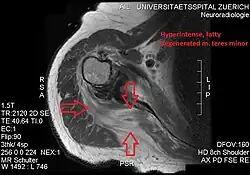

Atrophy of the teres minor muscle is often a consequence of a rotator cuff tear, but common isolated teres minor atrophies have also been found. A quadrangular space syndrome causes excessive and or chronically compression of the structures which pass through this anatomical tunnel. The axillary nerve and the posterior humeral circumflex artery pass through the space. People affected note shoulder pain and paresthesia down the arm first and foremost in abduction, extension, external rotation and overhead activity. Selective atrophy of the teres minor muscle has been seen and pulled together directly with compression of the corresponding axillary nerve branch or posterior humeral circumflex artery. Fibrous bands, cysts of the glenoid labrum, lipoma or dilated veins can occupy the quadrilateral space pathologically. Similar symptoms are common with anterior shoulder dislocation, humeral neck fracture, brachial plexus injury and thoracic outlet and inlet syndrome. It is important to include those pathologies for a complete as possible differential diagnosis.

Ultrasonography is a tool to detect a fatty degenerative atrophy of the teres minor and shows in affected muscles increased echogenicity and betimes a slight reduction in muscle bulk. MR imaging helps to consolidate the diagnosis of neurogenic muscle atrophy. Extracellular edema after traumatic events causing neural damage show an increased signal intensity on T2-weighted MRI sequences and normal intensity on T1-weighted sequences. Posterior humeral circumflex artery compression and reduced blood flow in stressful arm positions and or maneuvers can be diagnosed by a Doppler ultrasonography. The nerve should be detected adjacent to the vessel. In an elevated arm position the axillary neurovascular bundle can be seen at the posterior axillary fold just before it perforates the deltoideus, while the posterior course is well visible in the neutral position. For a detailed assessment of the artery, a MR angiography is required. The major task of an ultrasonographic examination is to rule out any space occupying mass. Additional electromyography is helpful to reveal any decelerated nerve conduction velocity, and thus denervation of the concerned muscle.[5]